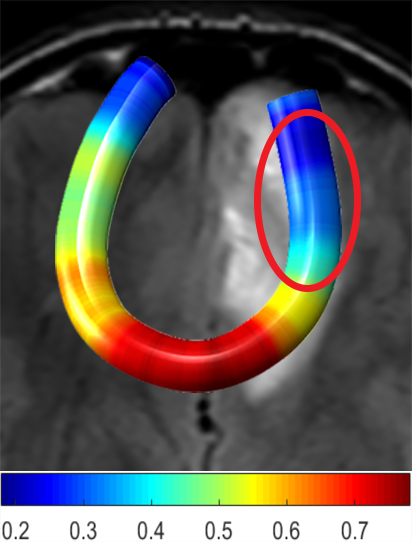

We performed pairwise comparison between two scans of a 32-year-old basketball player, diagnosed with mild occipital traumatic brain injury and frontal hemorrhage due to contrecoup impact, acquired one week and 6 months post-injury. The hemorrhagic lesion at the frontal right hemisphere of the player is no longer visible in the FLAIR image acquired 6 months after injury (Fig. 2a). Local differences between corresponding, longitudinal FA- and MD-FFDD profiles of the FMT (chosen due to its proximity to the lesion area) are shown in Fig. 2d. Figs. 2b-c present color-coded FMT to visually demonstrate these differences. Results show significant longitudinal variability at the right hemisphere part of the tract, corresponding to the lesion area, and relatively minor differences along the rest of the tract. These results should be considered as a proof of concept, validating the FFDD analysis results for the detection and localization of mTBI-related variabilities between fiber bundles.

| (a) FLAIR | (b) FA-FFDD | (c) MD-FFDD | (d) Local Differences |

FA-FFDD |